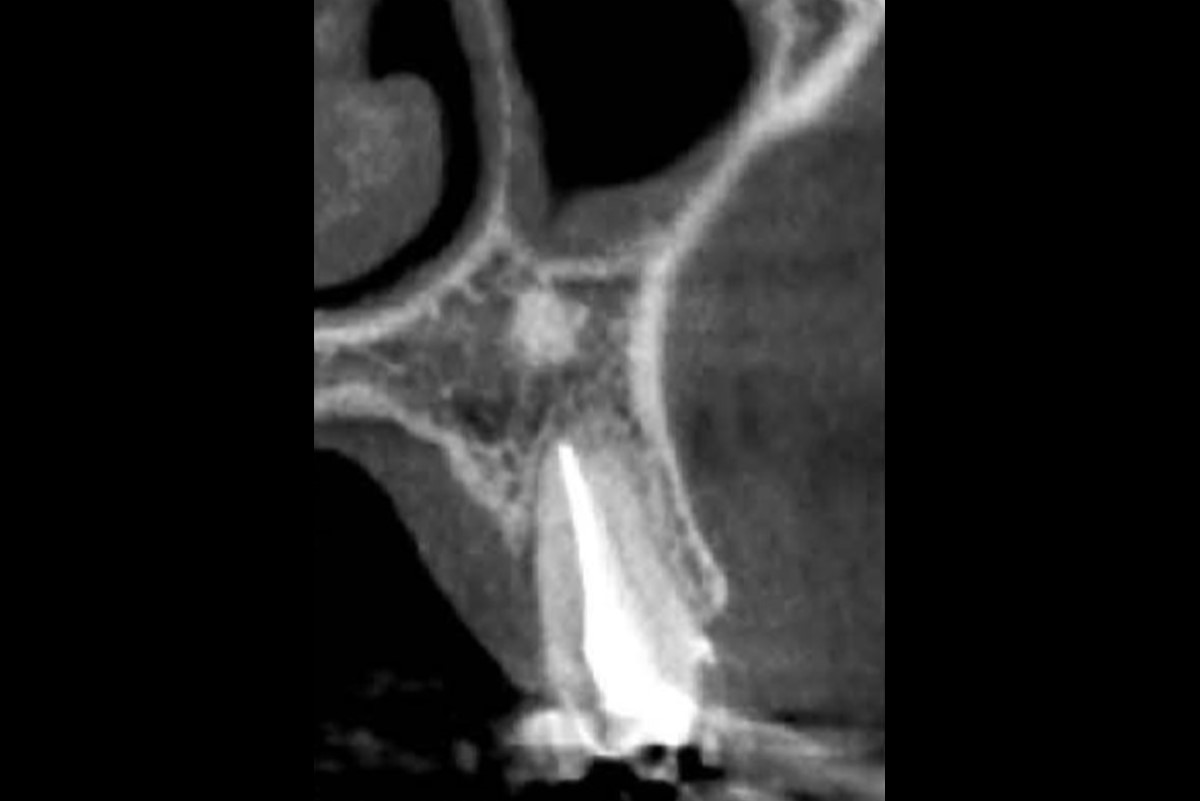

09/16 - 7 months postoperatively: CT scan and clinical view indicate full bone regenerationFull bone regeneration in extraction socket augmented with maxgraft® and Jason® membrane – Dr. C. Landsberg

10/16 - 7 months postoperatively: CT scan and clinical view indicate full bone regenerationFull bone regeneration in extraction socket augmented with maxgraft® and Jason® membrane – Dr. C. Landsberg

11/16 - 7 months postoperatively: CT scan and clinical view indicate full bone regenerationFull bone regeneration in extraction socket augmented with maxgraft® and Jason® membrane – Dr. C. Landsberg